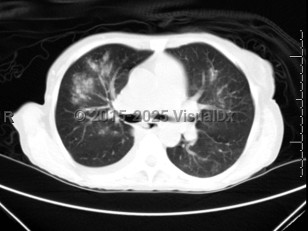

This viral illness may manifest differently depending on patient age, health status, and whether this is a primary infection or a secondary one. RSV symptoms in most patients are mild and consist of nasal congestion, rhinorrhea, sneezing, decreased oral intake, cough, and sometimes a fever. In younger patients, RSV may cause bronchiolitis (inflammation of the small airways in the lungs) or a viral pneumonia that presents with runny nose, irritability, wheezing, increased work of breathing, and hypoxemia. In very young infants, apnea may be one of the first presenting symptoms. RSV may also present as a croup-like illness with a barky cough and stridor. Among infants and young children with primary infection, the disease may present as LRTI with bronchiolitis or pneumonia. In 20% of infants presenting to the hospital, apnea may be the presenting symptom. Apnea is more likely to be seen in premature infants and in those with severe hypoxemia. Older children and adults are more likely to present with symptoms of URTI or tracheobronchitis. RSV is also known to be an important factor leading to acute otitis media in young children with bronchiolitis. However, in elderly or immunocompromised adults, these conditions may progress to a severe LRTI. In a study of adult SOT recipients, the most common symptoms were fever, cough, and dyspnea. Less common symptoms included rhinorrhea and wheezing.